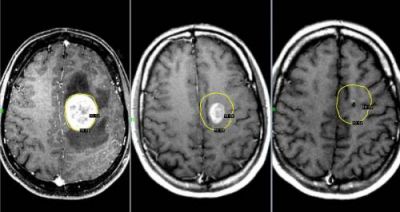

Рак мозга

При онкологическом заболевании мозга, у человека далеко не всегда болит голова. Но если такой симптом даёт о себе знать, болезнь протекает очень тяжело.

Головная боль, спровоцированная опухолью мозга, возникает по причине повышения внутричерепного давления. Чем быстрее растёт опухоль, тем сильнее повышается давление.

Возникает такой дискомфорт, преимущественно, утром. Практически всегда он сопровождается рвотой.

По мере прогрессирования заболевания, частота болевых приступов увеличивается, а дискомфорт становится сильнее.

Это приводит к тому, что больной быстро теряет вес, у него появляются судороги. При наличии симптомов рака мозга, следует незамедлительно обратиться к онкологу.

Если вовремя диагностировать заболевание, у больного есть все шансы на выздоровление. Однако если рак будет диагностирован на поздней стадии, шансы на успешное удаление злокачественной опухоли очень малы.

Опухоли мозга

Голова болит второй день помогает только таблеткаЭто новообразования, локализующиеся в тканях мозга. Могут носить доброкачественный и злокачественный характер. Доброкачественные опухоли не дают метастазов, имеют чёткие границы роста, лечатся безоперационным путём, не имеют рецидивов.

Злокачественные опухоли характеризуются быстрым прорастанием в другие ткани с их последующей трансформацией. При этом метастазы могут наблюдаться сразу в нескольких участках мозга.

Такие опухоли плохо лечатся, а на поздних стадиях их развития спасти человека практически невозможно.

Клиническая картина

Характер болевых ощущений — постоянный, по мере развития заболевания продолжительность приступов увеличивается. Когда человек двигается, болевые ощущения усиливаются. Сначала они локализуются в области опухоли, потом, по мере увеличения внутричерепного давления, переходят в лобную и затылочную часть. Наиболее сильный дискомфорт наблюдается в ночное и утреннее время из-за скопления жидкости. Вены не справляются с оттоком крови, поэтому к болям прибавляются отёчность и застои. Боли давящие, распирающие, пульсирующие.

К головным болям затем добавляется рвота. При физической нагрузке или кашле болевые ощущения усиливаются, появляется двоение в глазах, временами исчезает зрение. Голова кружится, у пациента нарушается координация движений. Могут неметь конечности, ослабляется тонус мышц.

Иногда бывают эпилептические припадки, путается сознание.

Вмешательство врача

Необходима помощь терапевта, нейрохирурга, онколога, онколога-радиолога.

Диагностирование

Для диагностики используется МРТ мозга, ПЭТ, КТ мозга, ангиография и другие методы.

Лечение

• Для облегчения боли на ранних стадиях заболевания врачи рекомендуют мочегонные препараты и кортикостероиды, с помощью которых удаётся добиться частичного снятия отёка и нормализации кровоснабжения на поражённом участке.

• Удаление опухоли с помощью лазера, эндоскопии и ультразвука.

• Иссечение опухоли. Метод травматичен. Способы иссечения: трепанация черепа или удаление костных фрагментов.